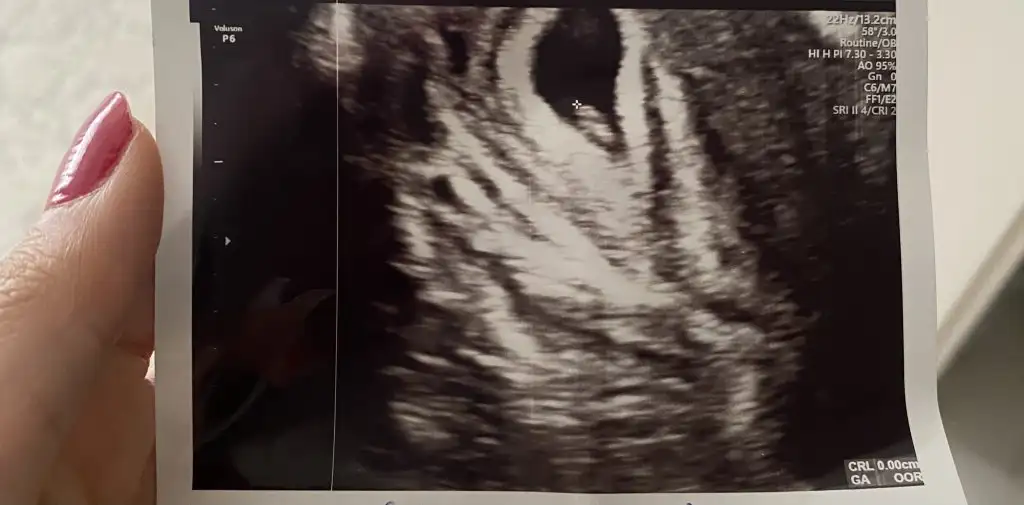

sen de yorumlar mısın bu 5. hafta vajinal ultrason

Sata göre 7+3 olduk usg göre 6+6. Hele minnoş.